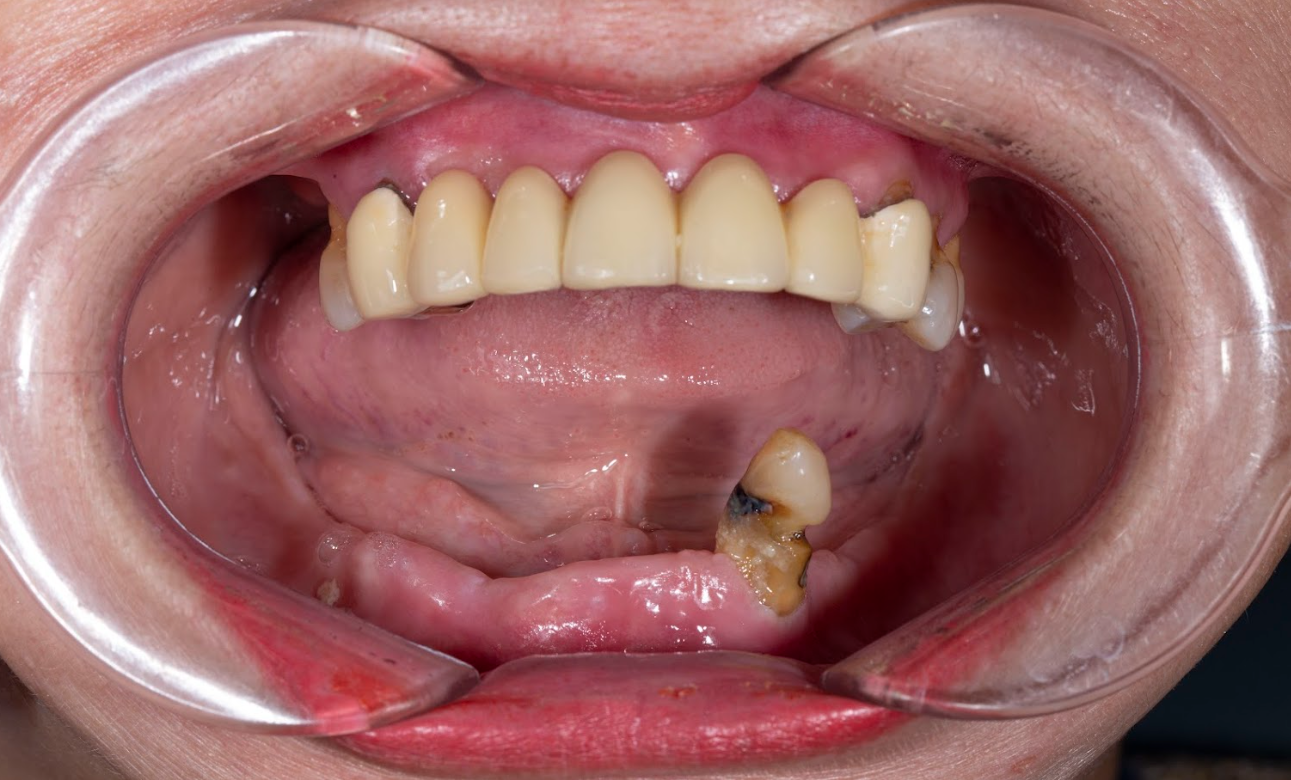

Ghép xương là kỹ thuật bổ sung thêm phần xương hàm đã bị tiêu, mỏng hoặc không đủ thể tích để đảm bảo trụ Implant có thể đặt vững chắc và tồn tại lâu dài trong xương hàm.

Kỹ thuật này được áp dụng phổ biến khi:

Bạn mất răng lâu năm.

Xương hàm đã bị tiêu xương nghiêm trọng do viêm, nhiễm trùng hoặc đeo hàm giả tháo lắp lâu ngày.

Bạn muốn trồng răng ở vị trí xương mỏng như vùng răng cửa hàm trên.

Tiêu xương nghiêm trọng (dưới 4–5mm chiều cao xương).

Muốn đặt trụ ở vị trí thẩm mỹ như răng cửa nhưng xương quá mỏng.